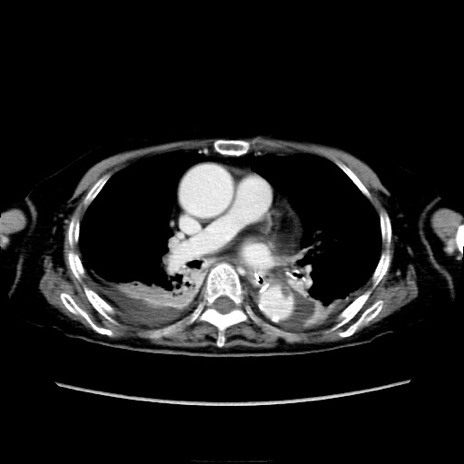

症例40(横断像)

横断像